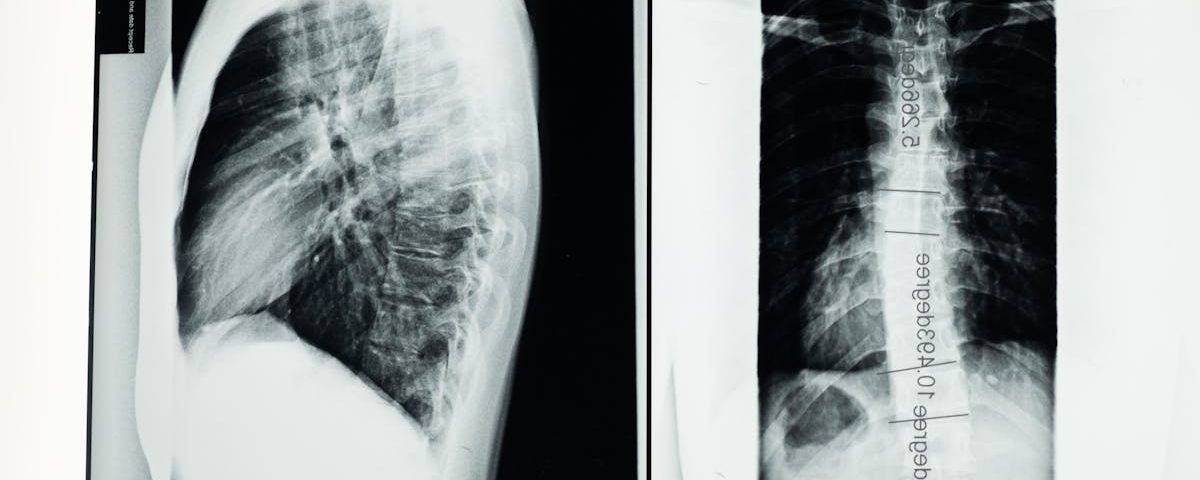

Quels examens permettent de diagnostiquer la sciatique?

Une IRM ou une radiographie est généralement nécessaire pour confirmer la cause de la sciatique.